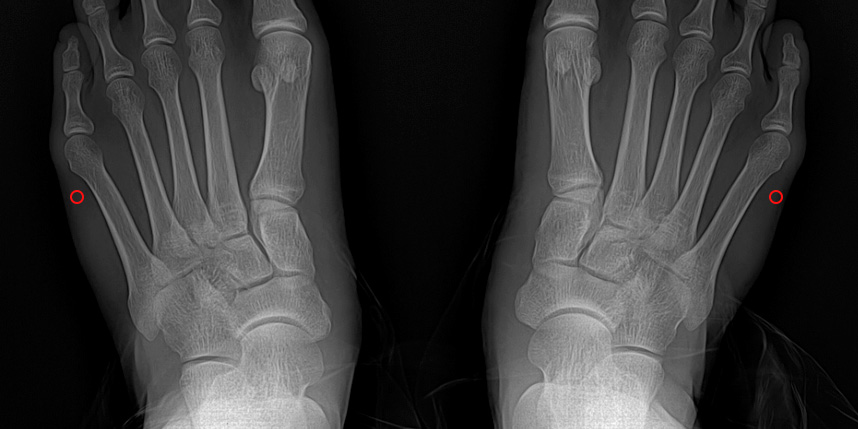

빨간 포탈을 이용하여 초음파 절골기를 삽입하여 절골을 하고 핀을 삽입합니다.

핀은 바깥으로 빼어 놓고, 6-8주째 외래에서 간단하게 제거합니다.

* 환자에게 받은 소중한 자료입니다.